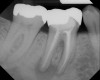

Figure 6  Root resorption secondary to orthodontic tooth movement.

Figure 6